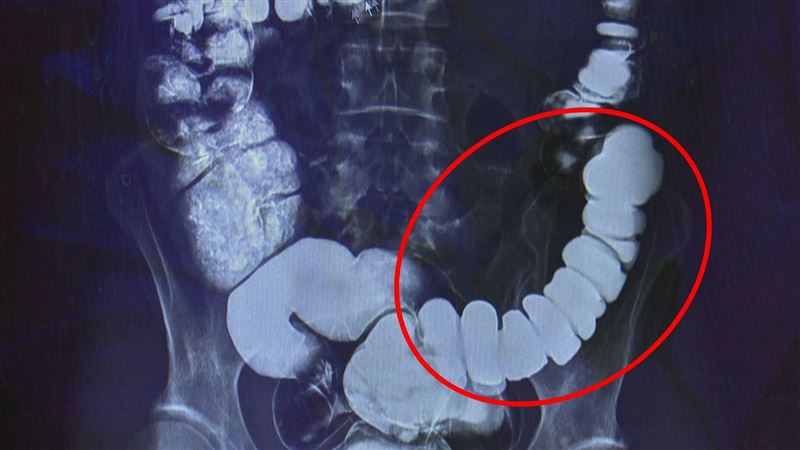

邱建銘主任從大腸攝影檢查發現,江小姐腸子繃得非常緊。這類典型情緒影響腸道的病例,臨床不算少,邱建銘仍驚訝:「沒看過把自己腸子逼得這麼緊的。」

▲邱建銘主任從大腸攝影檢查發現,江小姐腸子繃得非常緊。(圖/台中慈濟醫院提供)